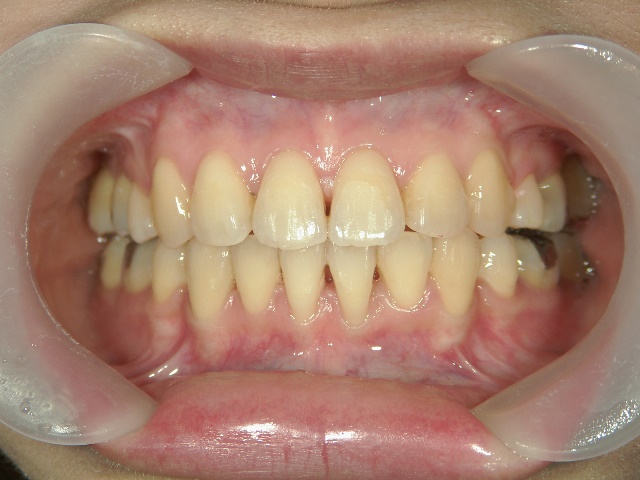

矯正歯科 治療前